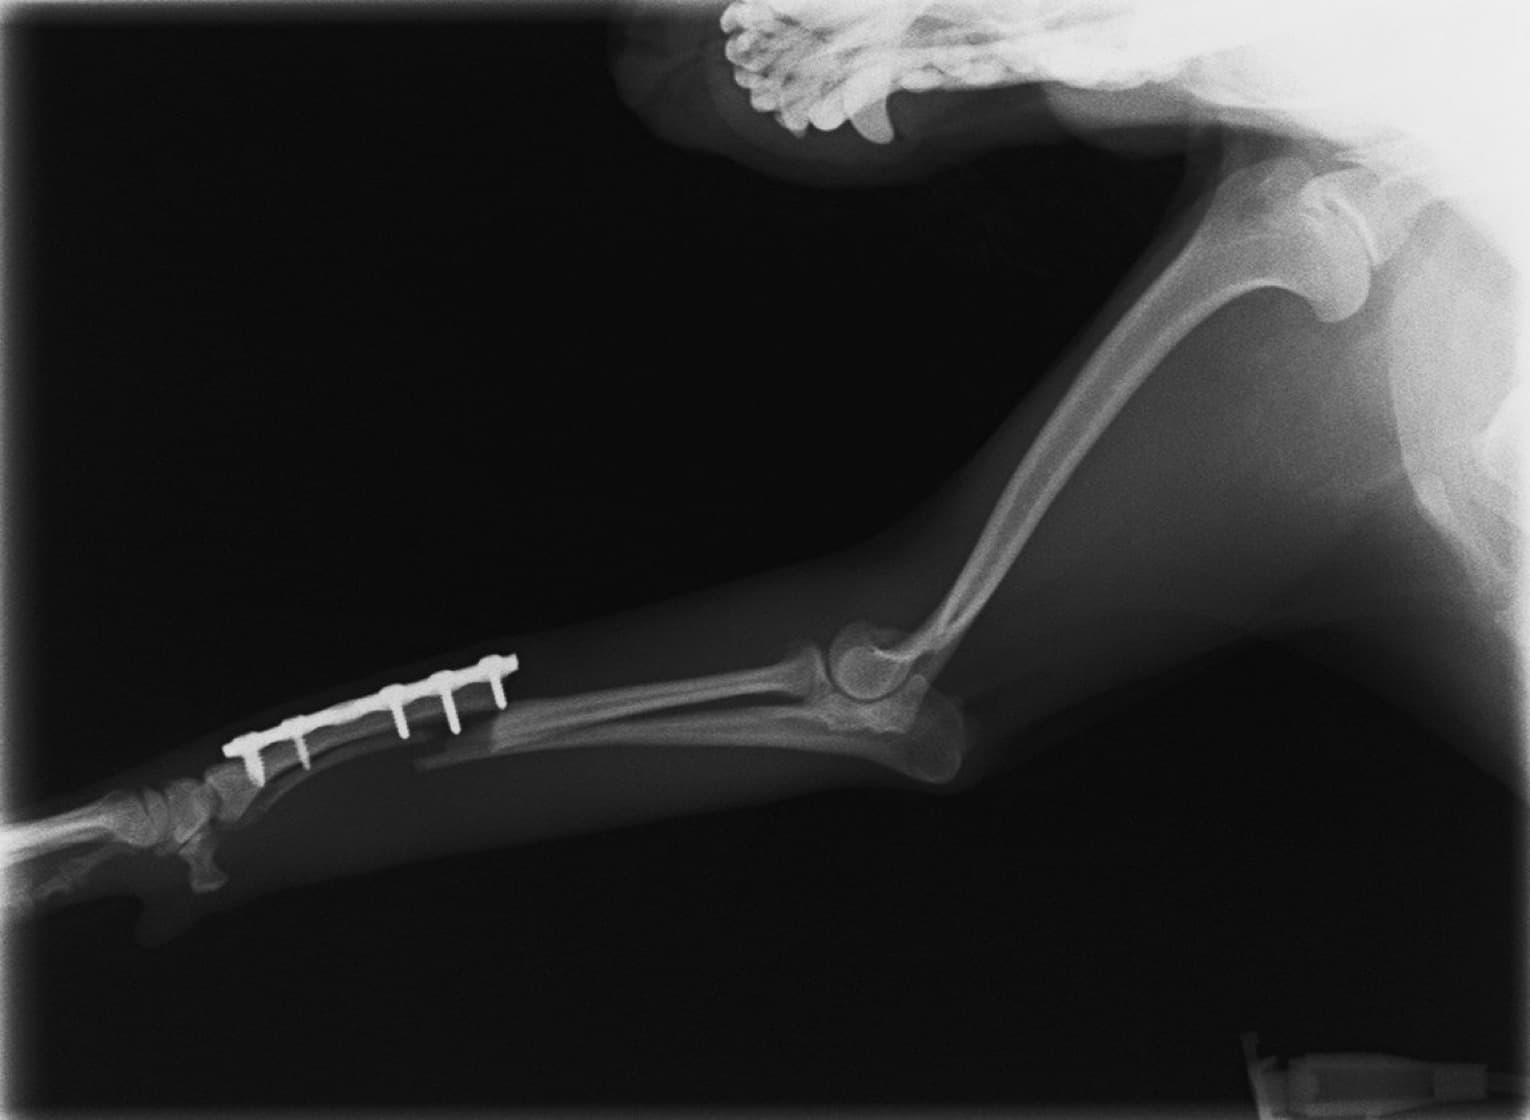

症例3:キルシュナーワイヤーのピンニングによる整復

ペルシャ猫 11ヶ月齢 雄

他院にて左大腿骨遠位の成長板骨折(salter-harrisⅠ型)が認められており、治療相談を目的として来院。当院にて、キルシュナーワイヤーを用いたピンニングにより骨折部位の整復を行いました。術後の経過は良好で、現在も経過観察中です。

術後レントゲン

Arthrex社のターゲティングデバイスを用いてピンニングの位置を調整することで、確実な固定を行っています。当院ではこの手術器具以外にも、人の手術にも使用される様々な器具を導入し、手術精度を高め、また医療メーカーと新しい器具の開発、試作にも取り組んでおります。